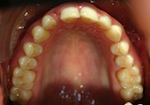

vorher

nachher

Patientin – 29 Jahre, Angle Kl. I, Invisalign für 9,5 Monate

Persistierender 52

(hier bereits entfernt)

12 war distal von 52 durchgebrochen